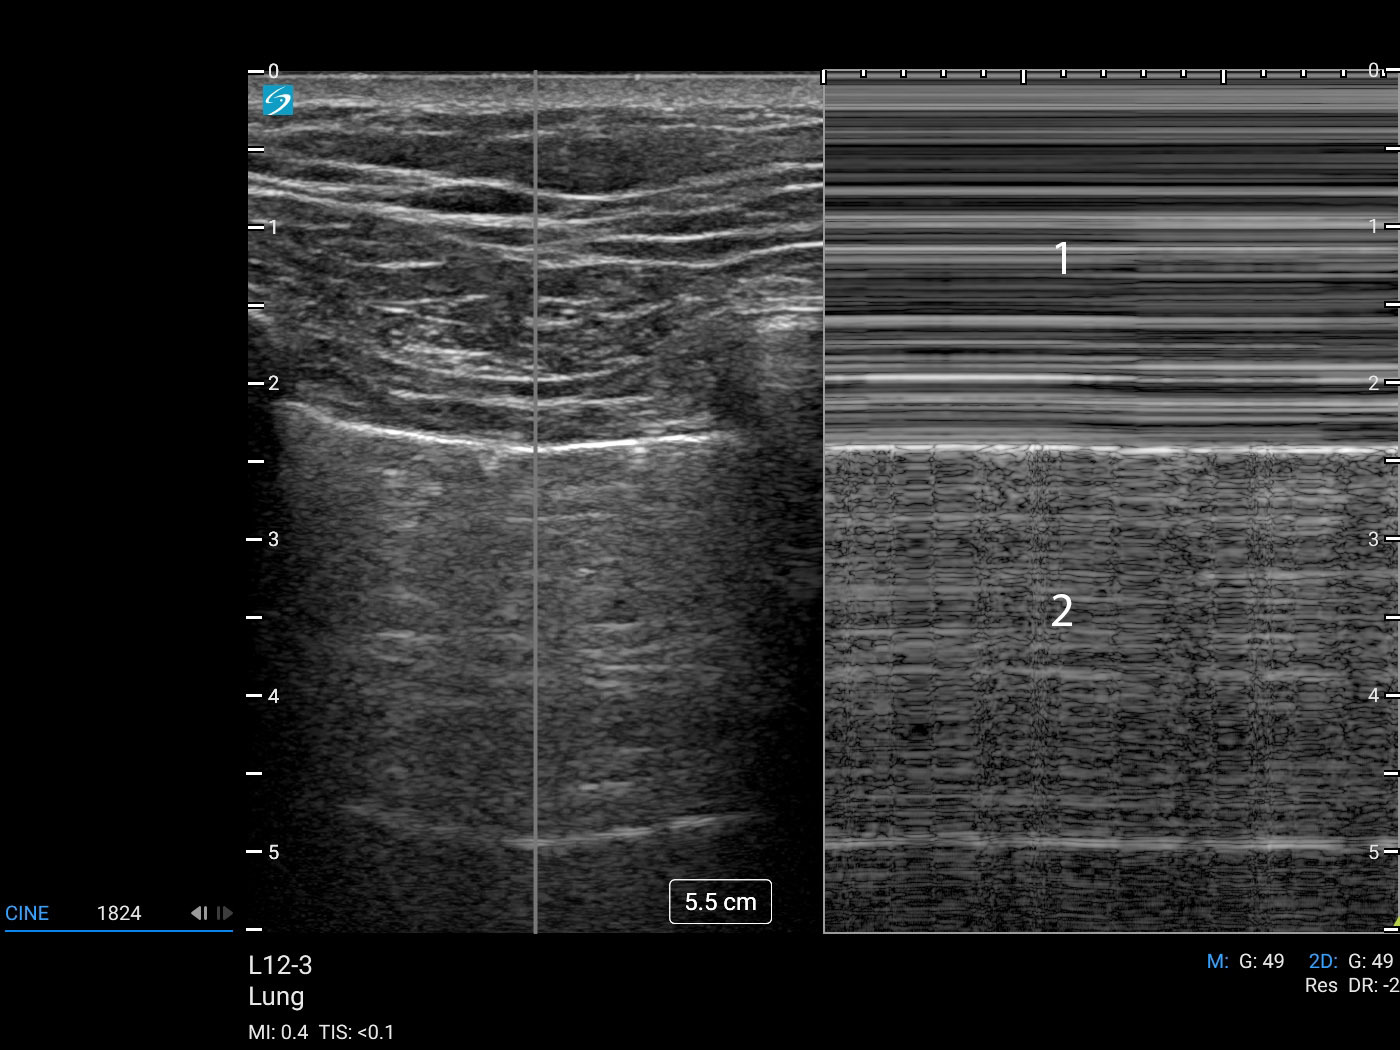

Lung M-Mode Linear (Sonosite PX L12-3) Image

Sea

Beach